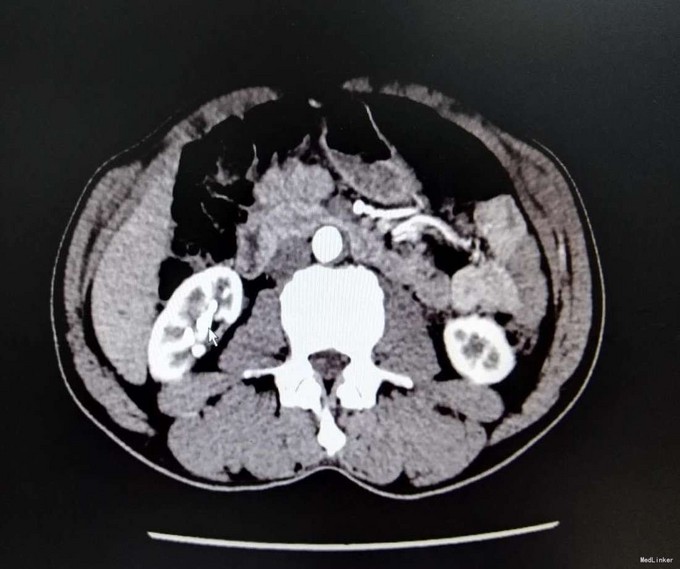

1、患者中年男性,慢性病程,既往有泌尿系结石史 2、患者2年前无明显诱因出现右侧腰部疼痛,疼痛呈放射状,阵发性,无恶心、呕吐,无尿频、尿急,尿痛,无排尿困难,无血尿、脓尿,我院门诊就诊,查KUB提示:右肾多发结石

3、查体:右肾区叩击痛(+),右侧肋脊点、肋腰点压痛(+),余查体未见明显异常 4、辅助检查:我院KUB提示:右肾多发结石,CTU平扫+增强:1、右肾多发结石,右肾下极局限性萎缩2、双肾多发囊张,3、肝多发囊肿

5、肾结石(右肾多发结石) 6、住院后完善相关检查,双肾CTU平扫+增强如上述,诊断为右肾多发结石,行右侧输尿管逆行置管术,手术顺利,术后恢复较好,顺利出院